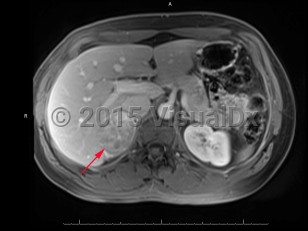

An adrenocortical carcinoma is a rare (1 case per 1 million adults) malignant tumor of the adrenal cortex. The tumor is typically unilateral and may have an irregular shape. Adrenal carcinomas may be found incidentally on imaging or may be identified after a patient shows signs of endocrine dysfunction, such as hypercortisolism or virilization. About half of adrenal carcinomas do not produce hormones, while the other half produce any combination of the normal adrenal cortical hormones. Adrenal carcinomas have a bimodal epidemiology. They are most common in children aged younger than 5 years and in middle-aged adults. Syndromes such as multiple endocrine neoplasia type 1 are uncommonly the cause of adrenal carcinoma.

Adrenocortical carcinoma has a chronic duration, lasting years. Prognosis varies based on staging of the cancer; however, nearly half of all patients have metastases at the time of initial diagnosis.